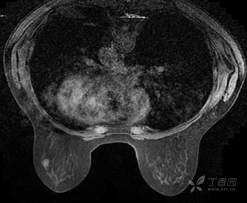

乳腺动态增强MRI 对比剂(钆布醇)

T2WI脂肪抑制序列

DWI

乳腺MR:左乳外上象限见T2WI高信号肿块影,大小约12mm×10mm×13mm,肿块为卵圆形,边缘模糊不规则;内部强化略不均匀;TIC曲线初始相呈快速强化,延迟期呈平台型;DWI呈高信号,ADC值为 0.000698 mm2/s。

因肿块边缘不规则,内部强化不均匀, TIC曲线初始相呈快速强化,延迟期呈平台型;DWI呈高信号,ADC值较低,考虑左乳外上象限肿块恶性不除外,BIRADS 4类。